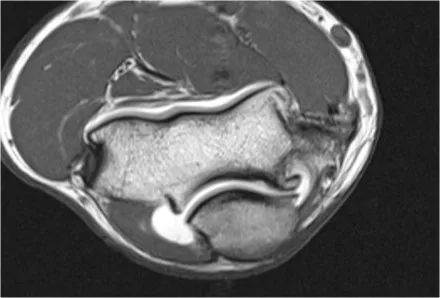

外侧副韧带

这里是外侧副韧带复合体的图示。它由桡侧副,侧尺侧副和环状韧带组成。

当您寻找桡侧副韧带时,首先要尝试识别常见的伸肌腱,因为在它下面你会发现桡侧副韧带(黄色箭头)。

当你向后走时,你会看到LUCL--侧面尺侧副韧带,它在桡骨头后面扫过(白色箭头)。环形韧带通常难以与RCL区分开,但有时可以在矢状MR-关节造影上识别。

我们可以从连续的冠状位MRI图像观察。

常见的伸肌腱起源于外上髁。在T1W图像上,肌腱应具有低信号强度(黄色箭头)。